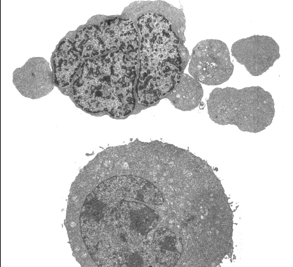

Apoptotic leukemia cell (upper panel) is rescued from dying when protein translation is activated (lower panel).